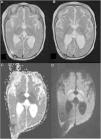

La RM se realiza por sospecha de malfunción valvular tras un mes de tratamiento con vigabatrina. Los hallazgos sugieren edema citotóxico: hiperintensidad de señal bilateral y simétrica en secuencias ponderadas en T2 en ambos tálamos, globos pálidos, núcleos dentados y troncoencéfalo (figs. 1A y B). En la secuencia de difusión se observa hiperintensidad de señal (fig. 1C) con caída del coeficiente aparente de difusión (ADC) en estas regiones (fig. 1C).

RM cerebral realizada a los 8 meses. A y B) Secuencia ponderada en T2 en la que se aprecia hiperintensidad bilateral de globos pálidos y tálamos. C) Mapa ADC que muestra restricción a la difusión de ambos globos pálidos y tálamos de forma simétrica. D) Imagen ponderada en difusión (DWI) en la que se observa hiperintensidad de globos pálidos y tálamos.